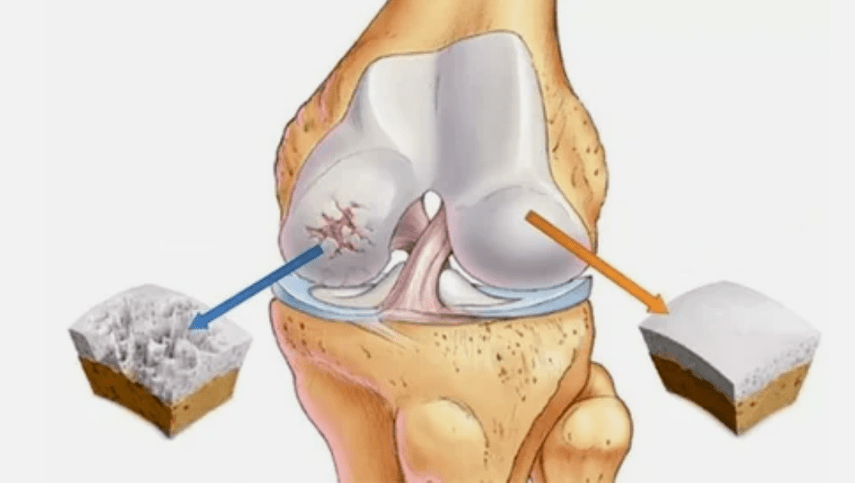

L'osteoartrite dell'articolazione si sviluppa a lungo, inizialmente colpisce solo Hyalink Norp e quindi si diffonde alle ossa, alla ciotola sinoviale, ai muscoli e all'intera capsula dell'articolazione. Nella prima o precoce fase dell'artrosi, la lesione si manifesta facilmente: un piccolo dolore dopo duro lavoro, gonfiore, arrossamento della pelle. A causa delle sensazioni ignoranti e spiacevoli vengono deformate, infiammate e porta grave dolore, il suo climax cade al mattino. La malattia è caratterizzata dalla scomparsa del dolore dopo lo sviluppo dell'articolazione. Se non trattata, una persona perde completamente la mobilità dell'articolazione.

Esiste una patologia dovuta a disturbi della funzione rigenerativa, dell'immunità o del danno meccanico. A causa di varie cause di cartilagine, diventa più sottile. In condizioni normali, il tessuto della cartilagine riceve una dieta sufficiente per il recupero, ma dopo eccessivo sforzo fisico o a causa di una violazione dei processi metabolici, le sostanze non hanno tempo per rigenerarsi. La mobilità comune rimane nella prima fase. Dopo aver considerato l'artrosi una definizione, vale la pena approfondire lo sviluppo della patologia in modo più dettagliato.

- La lesione primaria influisce sulla cartilagine ialina. Nel caso dei disturbi circolatori, c'è un deterioramento della forza patologica. È il primo passo o la prima causa che può verificarsi artrosi.

- Patologie di rivestimento ialina. Il diradamento della cartilagine porta alla sostituzione delle strutture ossee del tessuto patologico.

- La crescita anomale appare su cartilagine - osteofiti.

- La violazione che si verifica l'anatomia naturale della cartilagine e delle ossa porta al sovraccarico di aree di cartilagine sane. La distruzione dei tessuti articolari senza trattamento continua a guidare e porta a disabilità.

Se il grado di malattia aumenta, i processi patologici sono ancora peggiori. Alla fine, l'intero Hyalink Norp viene distrutto.